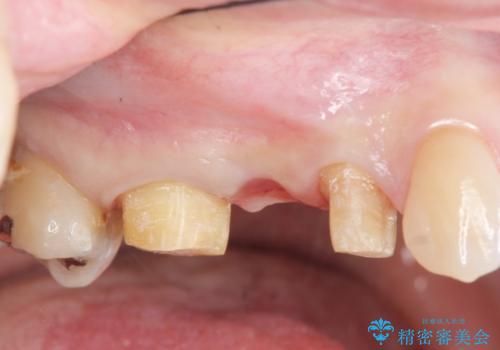

虫歯による歯の崩壊で歯を残すことが難しかったので抜歯を行い、インプラント・入れ歯ではなくブリッジによる咬合機能の回復を希望されました。

ブリッジは隣の歯を削り、クラウンにしなければならないというデメリットはありますがインプラントと異なり手術をしなくてもよく、入れ歯よりも一般的にしっかりと噛むことができます。